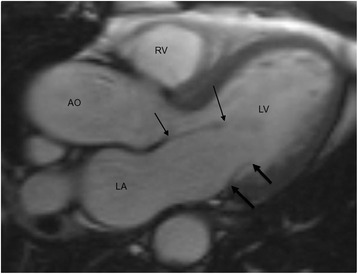

Fig. 1.

Measurement of mitral valve leaflets in 3-chamber diastolic image. Anterior mitral leaflet (AML) is indicated in thin arrows and posterior mitral leaflet (PML) in thick arrows. RV = right ventricle, LV = left ventricle, AO = aorta, LA = left atrium